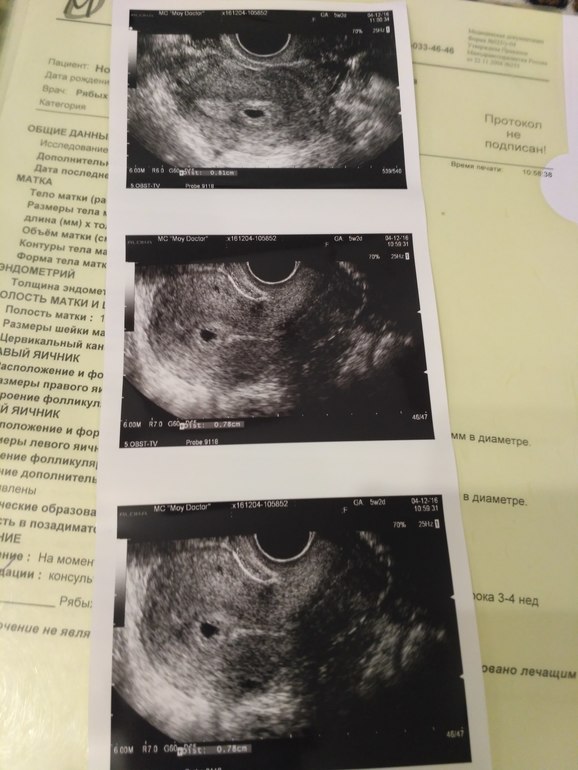

У нас получилось! Я беременна!Здравствуйте девочки! Ну вот теперь и я с вами! Все хорошо, в четверг втала на учет в ЖК, теперь жду скрининг, чтобы вновь увидеть нашего сладкого малыша. Всем желаю легкой беременности и родов без боли, ну и себе желаю конечно)) Сегодня была на УЗИ и теперь у меня есть первое фото моего пусяточки)